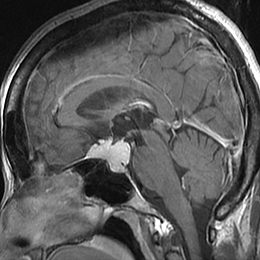

悪性腫瘍の手術前

手術後

放射線・化学療法後